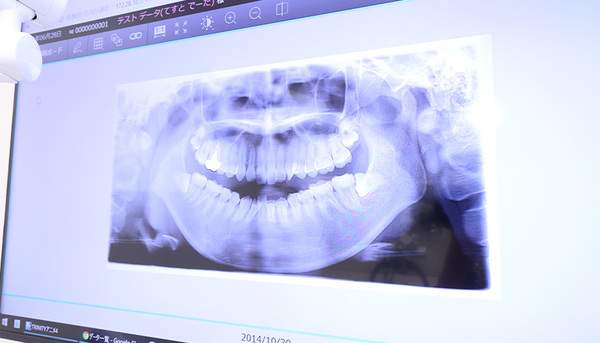

レントゲン撮影

虫歯になりかけの段階の診査が難しいときに撮影するレントゲン写真

歯と歯の間の虫歯は時として見えにくいことがあります。特に虫歯のできたてでは、診査が難しいです。そんなときは、レントゲンを撮影します。

レントゲンでみると、虫歯になっている部分は黒く抜けて写ってくるので、間違えることなくわかります。